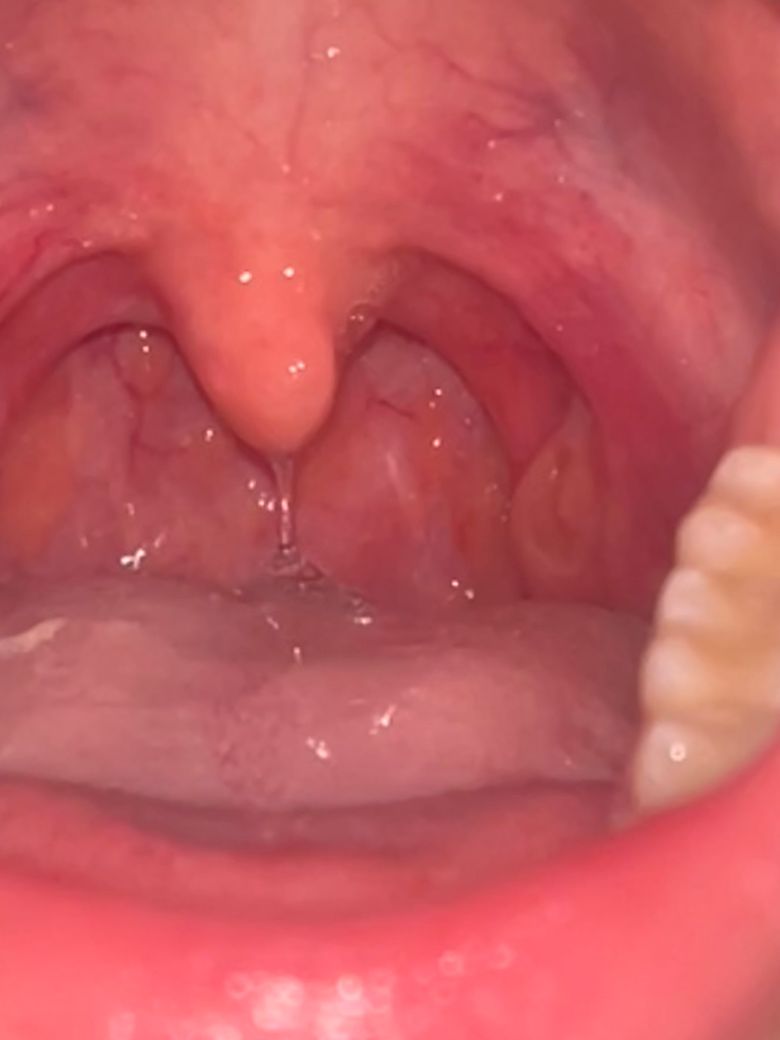

물을 계속 마셔도 (약 2리터) 목이 건조하고 편도염 걸렸을 때처럼 목안쪽이 약간 부은 느낌이 들어요. 찍어보니 뭔가 원래와 다른 것 같은데 병원에 가야하는지 어떻게 해야하는지 알려주세요

• 1번 째 사진

발적과 부종이 보입니다.

편도염 까지는 아니지만

인후염이 진행중인것으로 생각됩니다.

가까운 이비인후과를 내일꼭 가보셔요